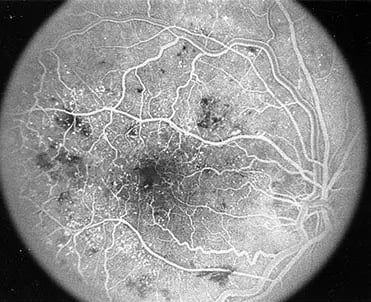

Fluorescein Angiography: A dye is injected into your arm, and photographs are taken of the retina to reveal blood vessel leaks or abnormalities.

Diabetic retinopathy is an eye condition that affects people with diabetes. It occurs when high blood sugar levels damage the blood vessels in the retina, leading to leakage, bleeding, and in severe cases, vision loss. There are two main stages of diabetic retinopathy:

Non-Proliferative Diabetic Retinopathy (NPDR): The early stage where blood vessels in the retina become weak and may leak fluid, but vision may remain unaffected.

Proliferative Diabetic Retinopathy (PDR): The advanced stage, characterized by the growth of abnormal blood vessels that can leak and cause retinal scarring, leading to vision impairment or blindness.

Diabetic retinopathy can also lead to diabetic macular edema (DME), a condition where fluid builds up in the macula, leading to blurry central vision.